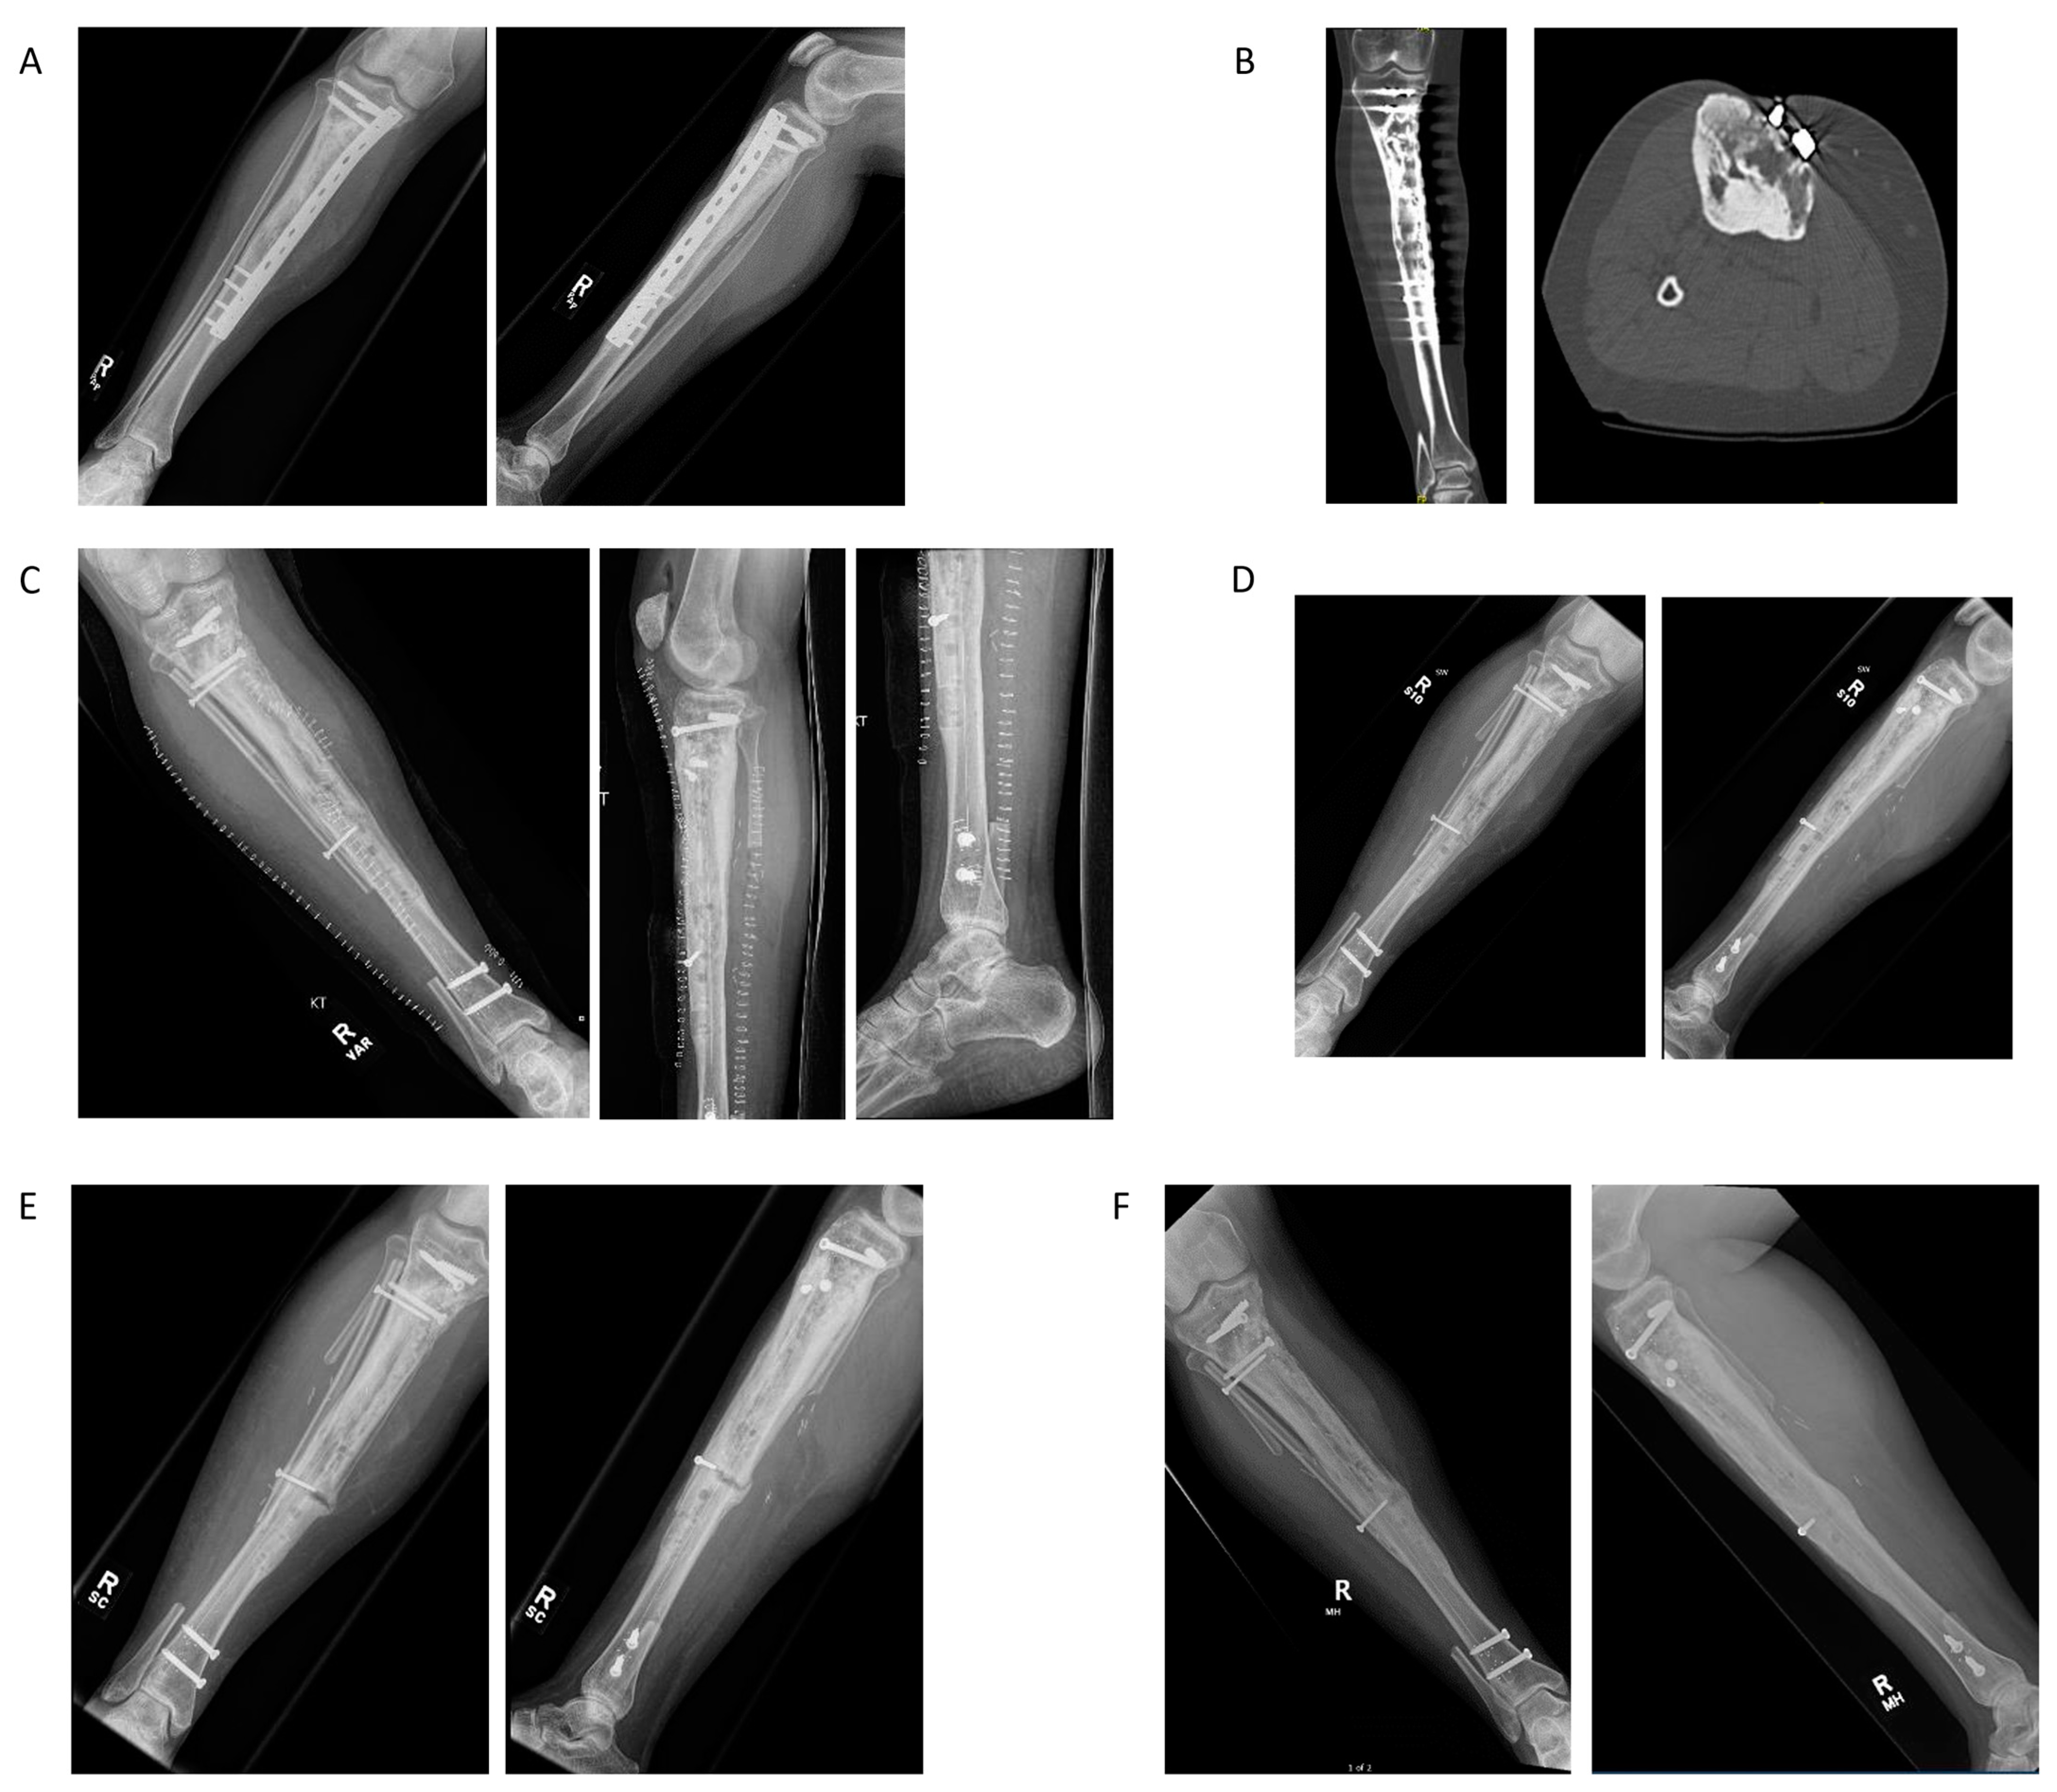

4.5. Case Example 5—Revision Plate and Nail Fixation with Fibular Autograft Augmentation of Prior Tibial Intercalary Allograft Failure